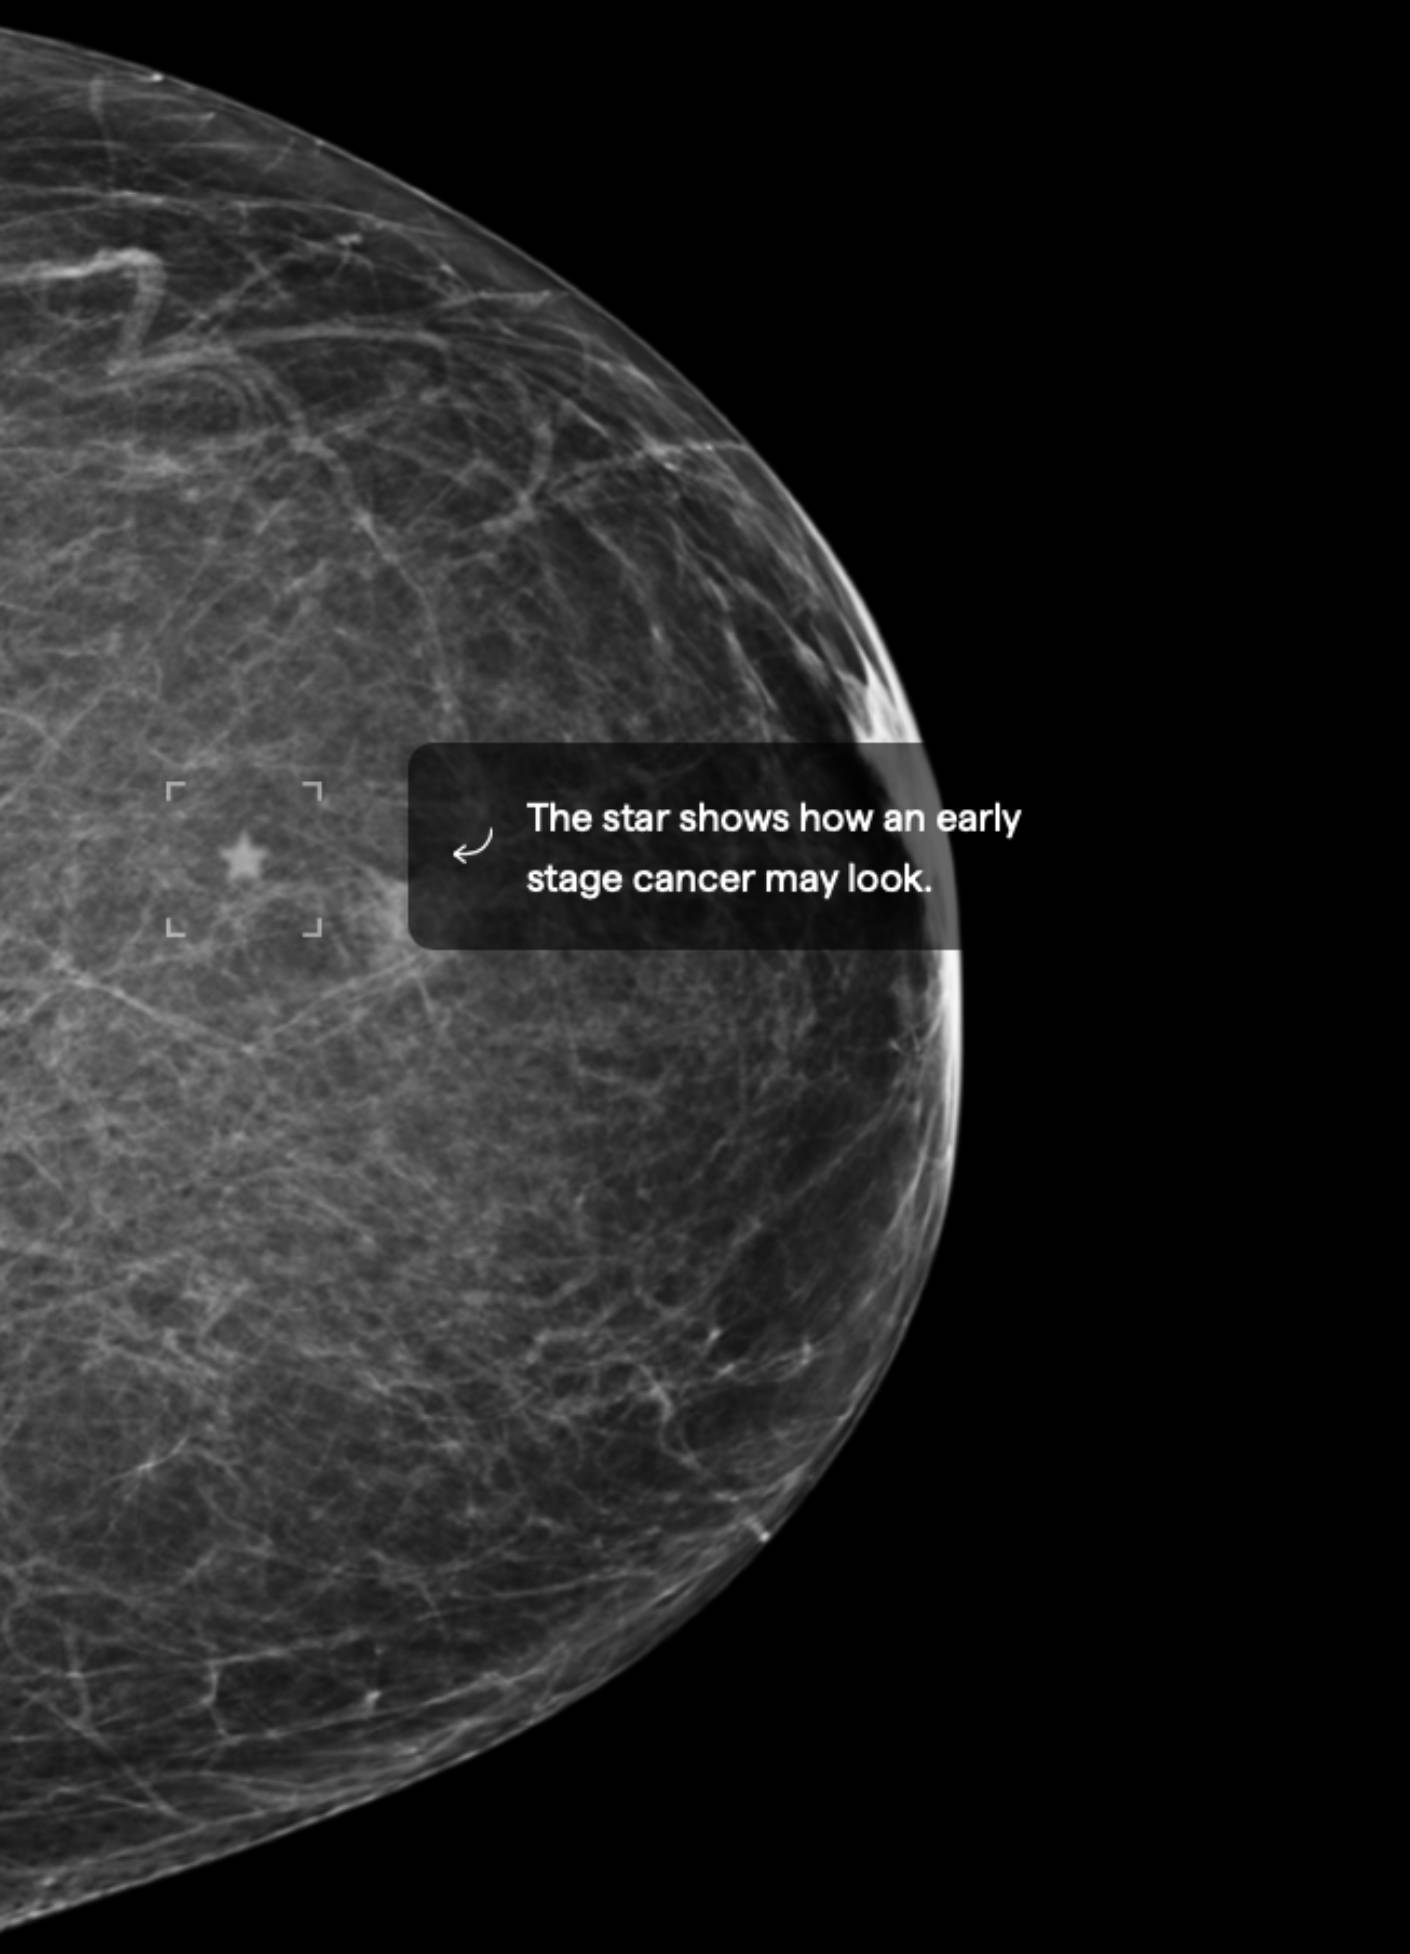

3.5% Mammographic Density

About 40% of female breasts fit category “B”. They are referred to as breasts with “scattered areas of fibroglandular density”.1

If you are over the age of 40 and in good health, an annual mammogram is recommended.2 Also consider asking your doctor about a risk assessment to help both of you better understand your lifetime risk for breast cancer.